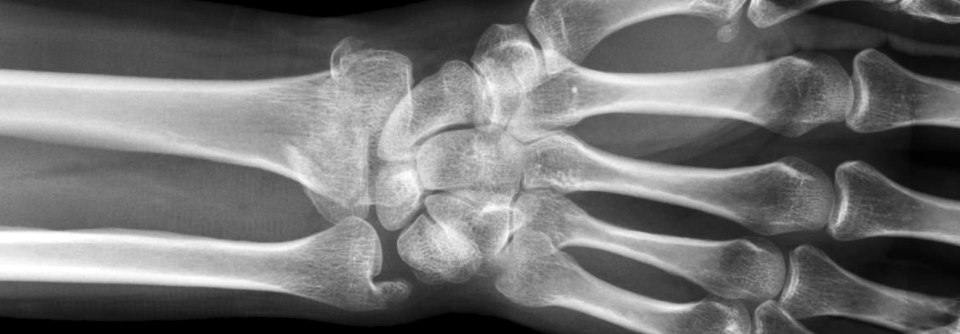

Bandscheibenvorfall

Wurzelbehandlung im Lendenbereich

Radikuläre Beschwerden aufgrund eines ­Bandscheibenvorfalls haben eine relativ gute Prognose – meist kommt es früher oder später zu einer spontanen…

Orthopädie , Chirurgie